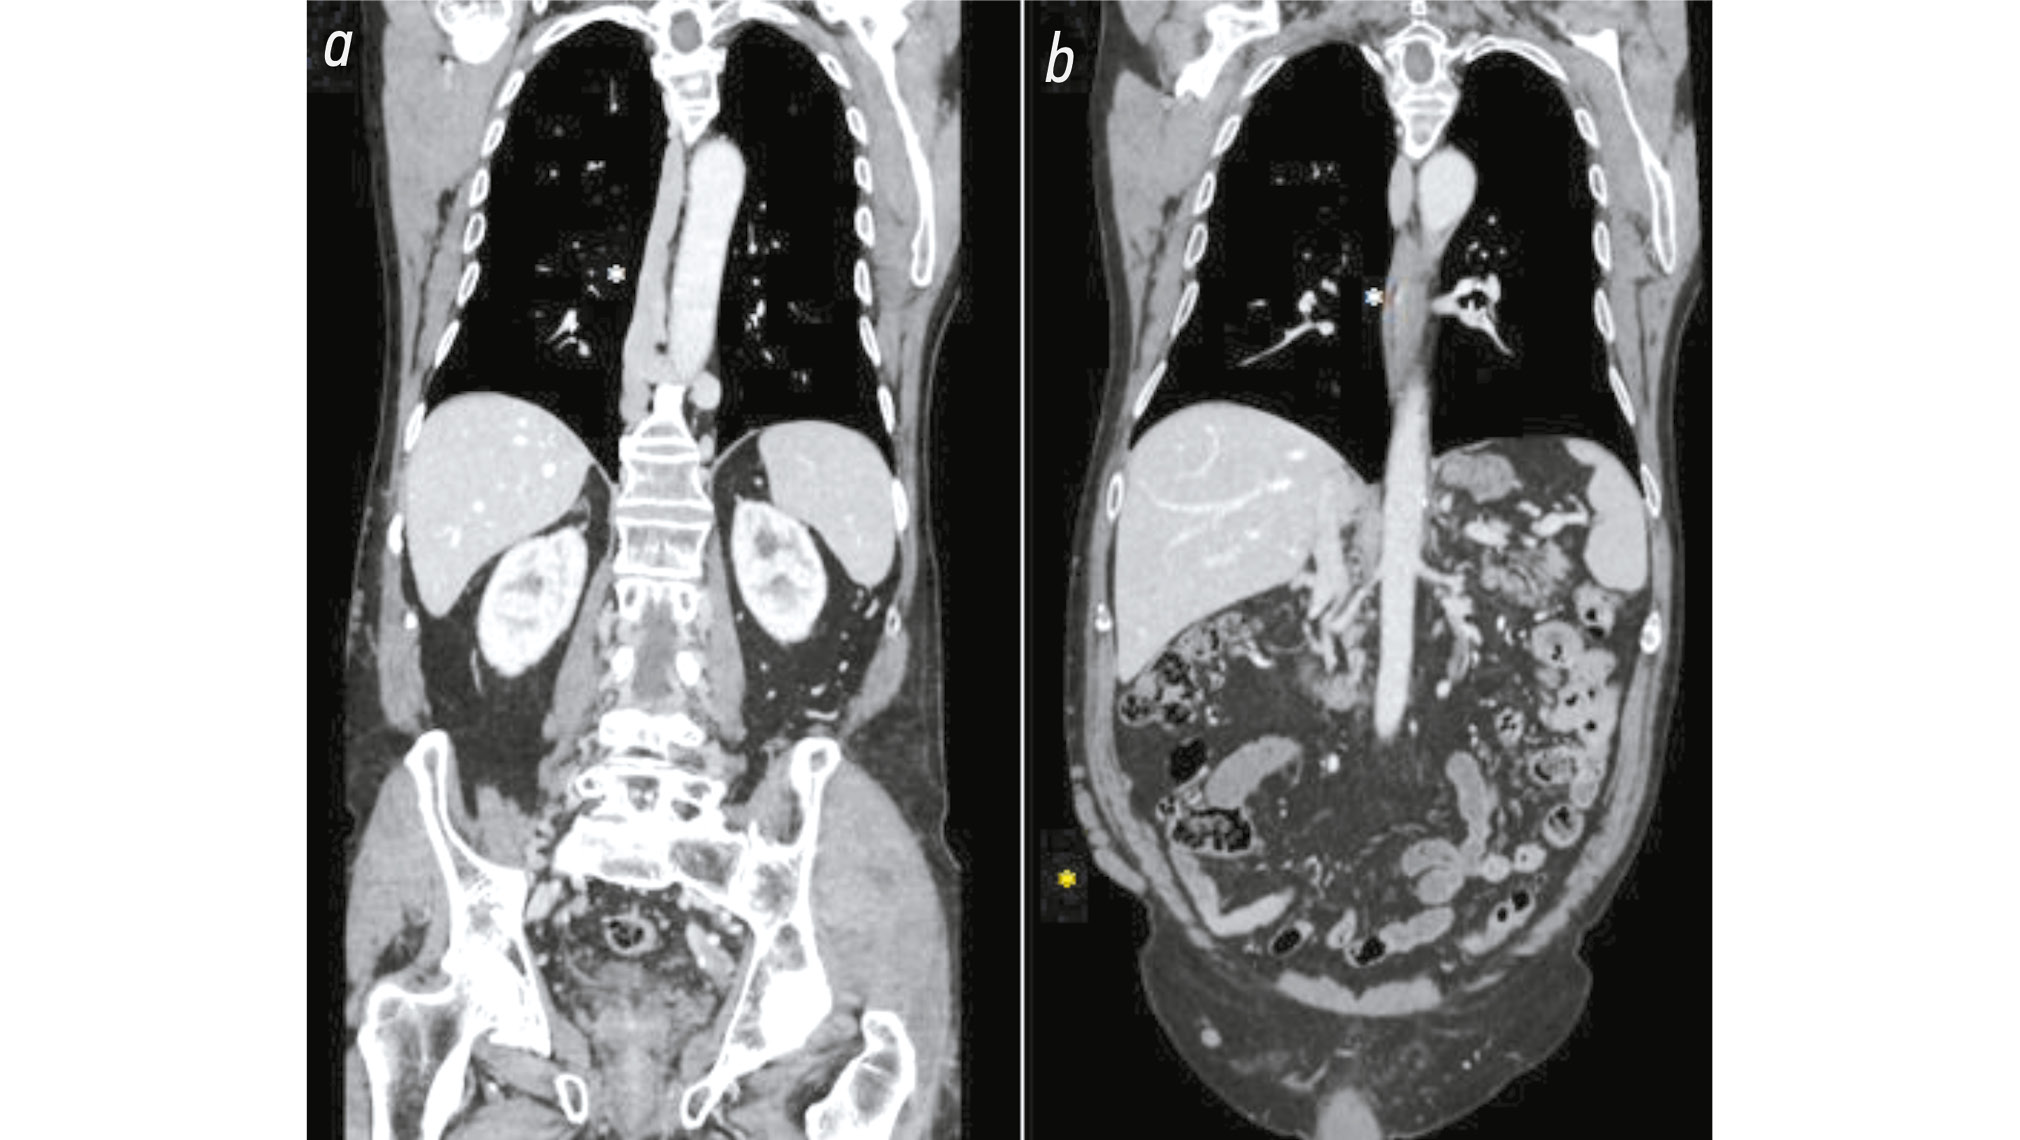

Certain distended azygos and hemiazygos veins received blood from the abdomen. The azygos vein connected with the superior vena cava (SVC) through its arch; however, its dimensions were abnormal. It began from D7 and extended to D10–11, from the confluence of the right renal vein, transhepatic vein, and an aberrant vein (Fig. 3 and Fig. 4).

Fig. 3. Computed tomography images of the coronal section and portal phase of the chest and abdomen: a) The white asterisk indicates the confluence of the giant azygos, hemiazygos, and an aberrant vein. b) Same image at different sections. The yellow asterisk on the right side at the level of the anterior abdominal wall indicates marked collateral vein circles.